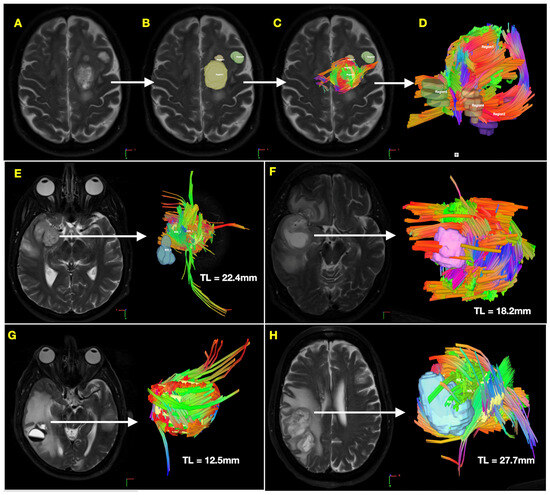

3.4. Reconstruction of GSC Distribution in PDX Mice Mirrors Tumor-Associated Tractography